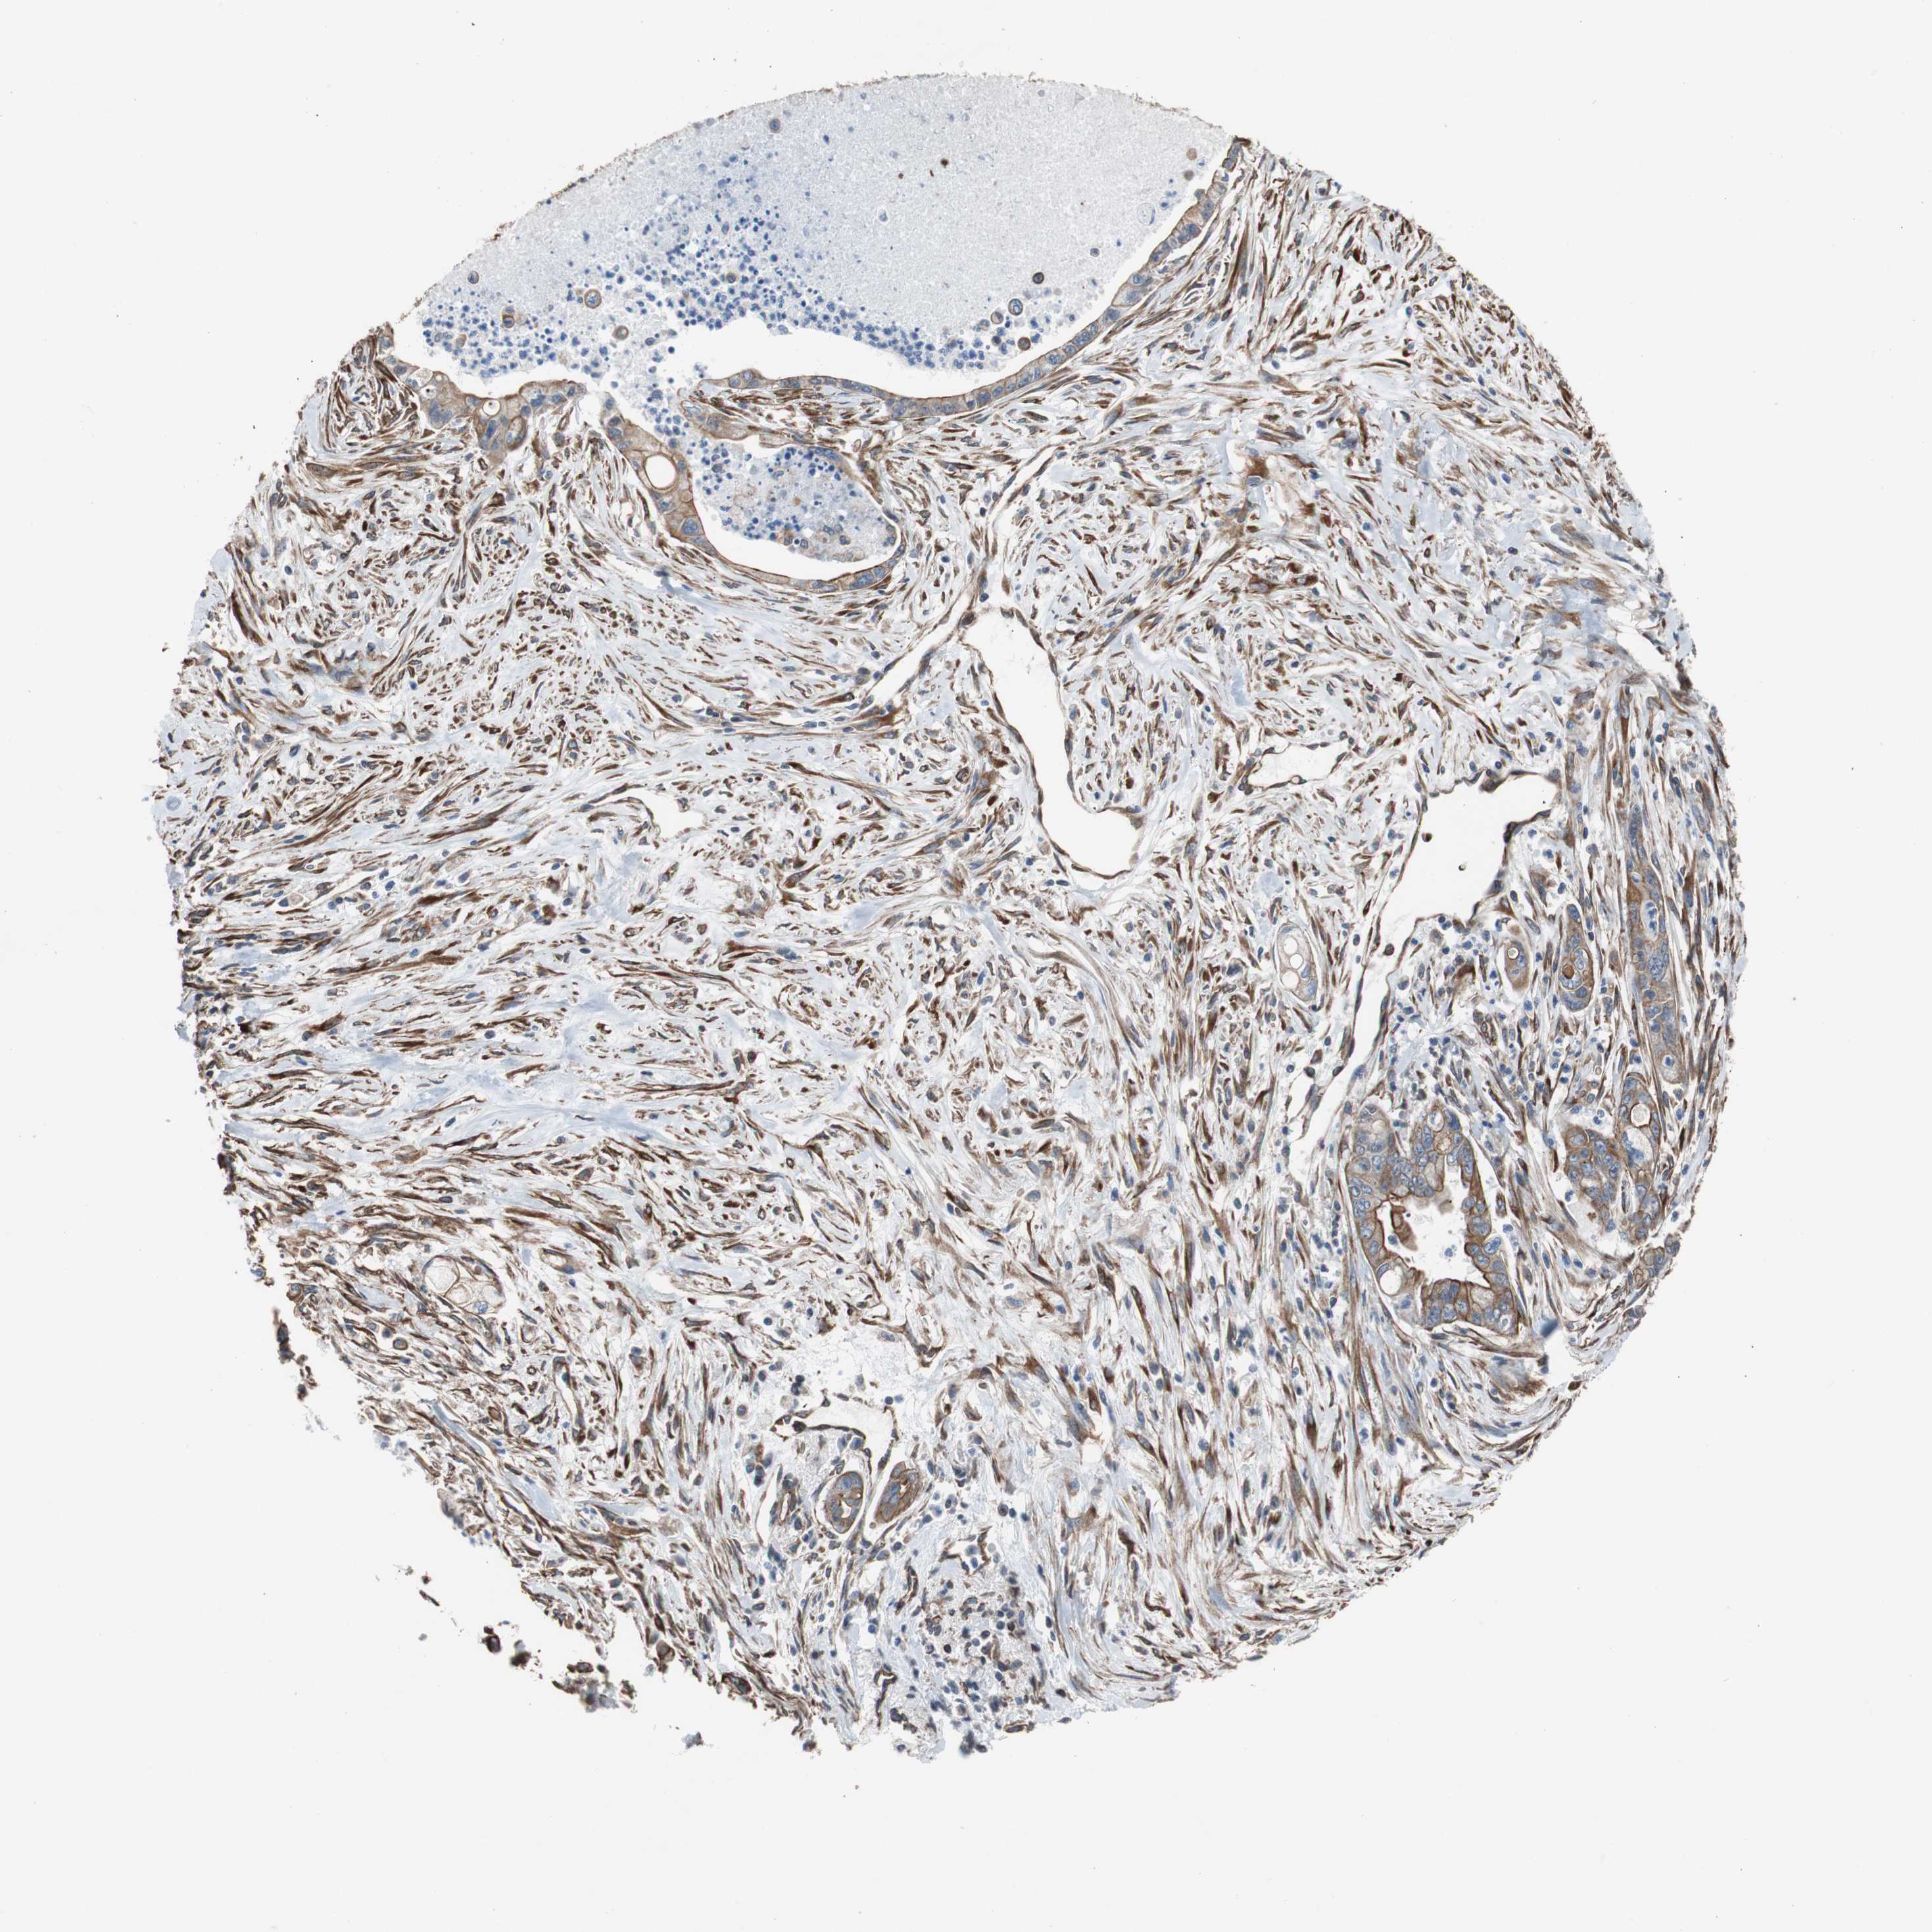

PANCREATIC CANCER - Protein expressioni

A mouse-over function shows sample information and annotation data. Click on an image to view it in a full screen mode. Samples can be filtered based on level of antibody staining by selecting one or several of the following categories: high, medium, low and not detected. The assay and annotation is described here.

Note that samples used for immunohistochemistry by the Human Protein Atlas do not correspond to samples in the TCGA dataset.

Antibody stainingi

Antibody staining in the annotated cell types in the current human tissue is reported as not detected, low, medium, or high, based on conventional immunohistochemistry profiling in selected tissues. This score is based on the combination of the staining intensity and fraction of stained cells.

Each image is clickable and will lead to virtual microscopy that enables deeper exploration of all samples and also displays staining intensity scores, fraction scores and subcellular localization as well as patient and tissue information for each sample.

Antibody HPA007119

Staining

High

Medium

Low

Not detected

Intensity

Strong

Moderate

Weak

Negative

Quantity

>75%

75%-25%

<25%

None

Location

Nuclear

Cytoplasmic/membranous

Cytoplasmic/membranous,nuclear

Adenocarcinoma, NOS

Adenocarcinoma, metastatic, NOS